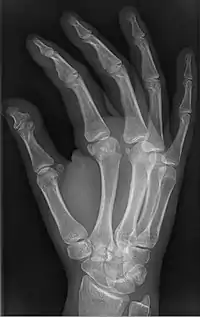

| Brachyphalangy of the thumb's distal phalanx, also known as brachydactyly type D, with otherwise normal phalanges of the 2nd-5th digits | |

Brachyphalangy of the distal phalange of the thumb

This condition is caused by either fusion or early closure of the phalange's growth plate. One example is brachydactyly type D, which is caused by an early closure of the thumb's distal phalange, leading to a congenitally short thumb with a similarly short and wide thumb nail.